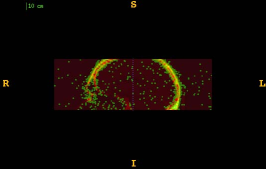

Figure 1 shows the examples of pixel selection masks generated using tested approaches at the highest resolution level for pixel sampling rate 0.5%. It is obvious that the samples generated with the URS approach are extremely spread, whereas the samples generated with the GMS approach are overly concentrated along the gradient magnitude structures present in the image. The proposed approach produces samples that balance those two extremities.